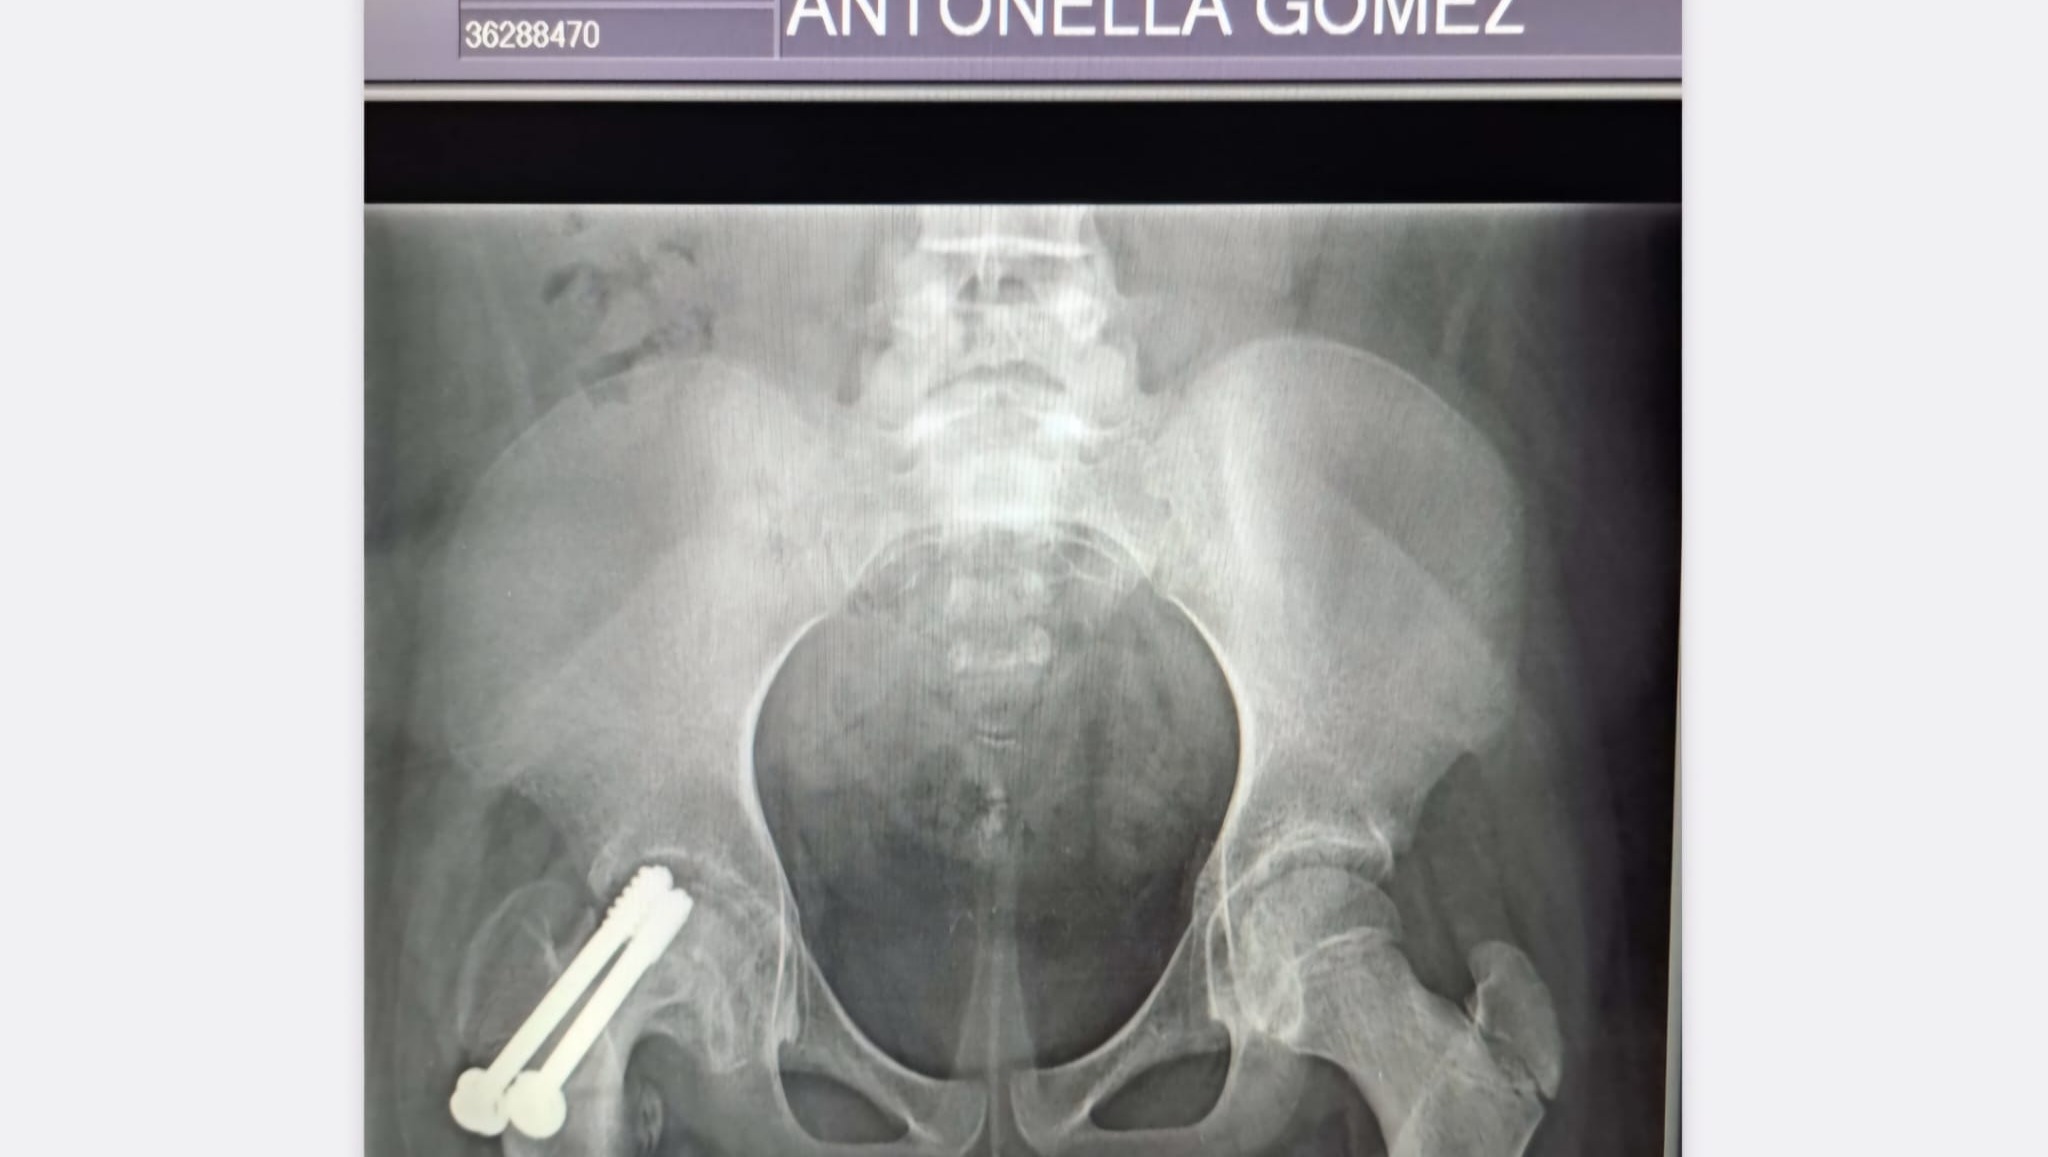

Sin embargo, su recuperación aún no ha terminado. Los médicos han indicado la necesidad de una tercera cirugía, ya que lamentablemente la cabeza femoral afectada sufrió una necrosis asintomática, lo que no solo generó un acortamiento de su pierna derecha, sino que también hizo que el material de soporte colocado en la última cirugía se desplazara, comprometiendo seriamente el acetábulo de su cadera. Esta nueva intervención es crucial para garantizar su estabilidad física y prevenir mayores complicaciones. El costo de esta cirugía asciende a USD 2.480, una suma que, sinceramente, no podemos asumir por nosotros mismos.

However, her recovery journey isn’t over yet. Doctors have recommended a third surgery as the next crucial step. Unfortunately, the affected femoral head has developed asymptomatic necrosis, resulting in shortening of her right leg and displacement of the support material inserted in the last surgery, which has severely compromised her hip socket. This surgery, essential to ensure her physical stability and prevent further complications, costs $2,480—a sum we cannot afford on our own.